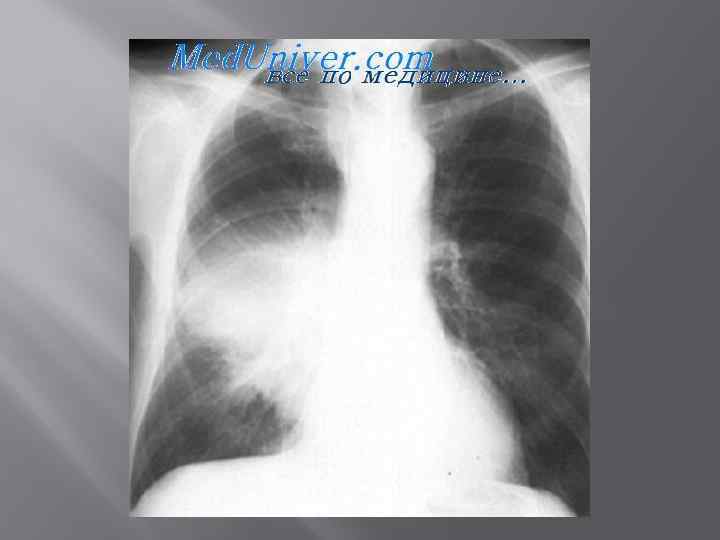

Рентгенограмма больного с правосторонней легионеллезной пневмонией.